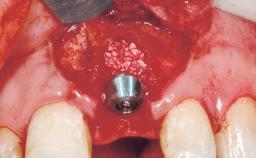

Late Placement of an Implant in a Maxillary Left Central Incisor Site

A 36-year-old female patient was referred for the replacement of the upper left central incisor (tooth 21), which had fractured. Although the tooth had been asymptomatic for many years, the crown began to loosen, at which time she presented to her dentist for an assessment. Teeth 21 and 22 had both been endodontically treated many years previously. She was a healthy individual and a non-smoker.

| Bone Volume | Deficient horizontally, requiring prior grafting |